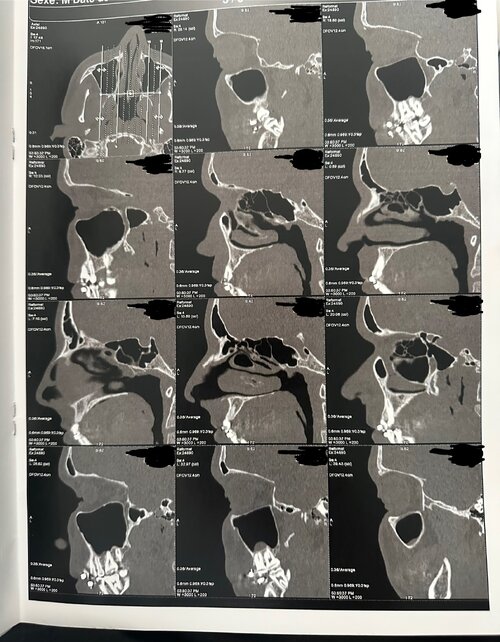

The CT scan provides a detailed view of the upper airway, nasal passages, and palate from multiple angles (axial, coronal, and sagittal). Based on the visible structures, several key anatomical features can be observed that relate to breathing efficiency, oral posture, and orthodontic development.

3. Airway and Oral Space

The sagittal (side) views reveal a moderately sized airway, with no extreme constriction but signs of limited space behind the soft palate and tongue. The soft palate extends close to the back wall of the throat (posterior pharynx), which may slightly narrow the oropharyngeal space. The tongue appears positioned relatively low, likely adapting to the narrow, high-arched palate, which offers limited lateral room for rest posture.

Together, these features suggest an airway that is functional but not maximally open, meaning airflow could be mildly restricted, particularly during sleep or nasal congestion.

5. Summary of Findings

The CT scan shows a well-developed craniofacial structure but with signs of maxillary constriction and mild airway limitation that could be improved through guided expansion. While this analysis cannot replace a professional diagnosis, it suggests that palatal expansion could offer both functional and structural benefits — particularly if nasal breathing, sleep quality, or crowding are concerns.

A final treatment plan should be based on a full orthodontic and ENT evaluation, including assessments of suture fusion, growth status, and respiratory function.

The CT scan provides a detailed view of the upper airway, nasal passages, and palate from multiple angles (axial, coronal, and sagittal). Based on the visible structures, several key anatomical features can be observed that relate to breathing efficiency, oral posture, and orthodontic development.

3. Airway and Oral Space

The sagittal (side) views reveal a moderately sized airway, with no extreme constriction but signs of limited space behind the soft palate and tongue. The soft palate extends close to the back wall of the throat (posterior pharynx), which may slightly narrow the oropharyngeal space. The tongue appears positioned relatively low, likely adapting to the narrow, high-arched palate, which offers limited lateral room for rest posture.

Together, these features suggest an airway that is functional but not maximally open, meaning airflow could be mildly restricted, particularly during sleep or nasal congestion.

5. Summary of Findings

- The palate is high and narrow, contributing to a slightly constricted nasal floor.

- The airway is moderate in size, with minor potential narrowing behind the soft palate.

- Sinuses appear clear, and septal deviation is minimal.

- These features are consistent with a skeletal pattern that may benefit from transverse expansion, depending on suture flexibility.

- Expansion options at this age often include MARPE or SARPE for meaningful skeletal change.

The CT scan shows a well-developed craniofacial structure but with signs of maxillary constriction and mild airway limitation that could be improved through guided expansion. While this analysis cannot replace a professional diagnosis, it suggests that palatal expansion could offer both functional and structural benefits — particularly if nasal breathing, sleep quality, or crowding are concerns.

A final treatment plan should be based on a full orthodontic and ENT evaluation, including assessments of suture fusion, growth status, and respiratory function.